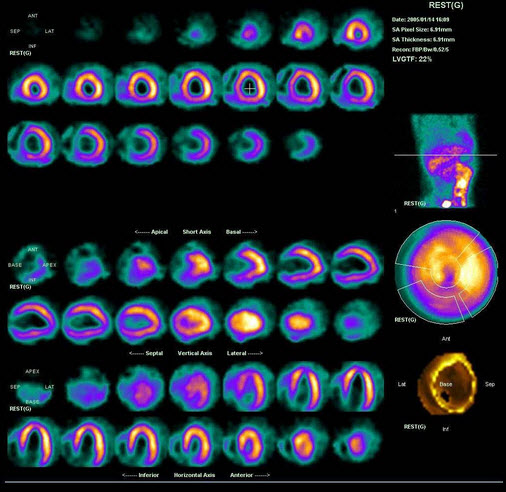

A.双侧肾上腺髓质增生

男性,43岁,1月前广泛前壁心梗,行溶栓治疗。行静息-硝酸甘油介入心肌显像如图,可能的诊断是()

A.左室心尖、间壁、部分前壁心梗

B.心梗区无存活心肌

C.左室外侧壁严重缺血

D.左室下后壁缺血

E.心尖心梗区有存活心肌